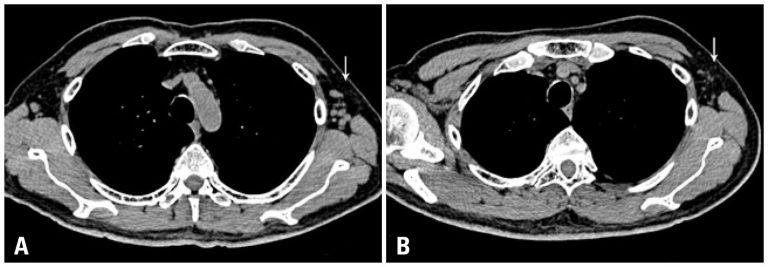

Coral reef aorta is described as an uncommon entity characterized by the presence of coarse calcifications, which are developed in the visceral aorta. These calcifications grow toward the lumen of the artery and can result in significant stenosis, so that causing malperfusion of the lower limbs, visceral ischemia or hypertension secondary to renal involvement. We report here a case of a 54-year-old patient with coral reef aorta and symptomatic. The clinical presentation of the patient required the surgical approach. A […]

Keywords: Aorta; Aorta, abdominal; Atherosclerosis; Case reports; Emergencies; Endarterectomy; Ischemia